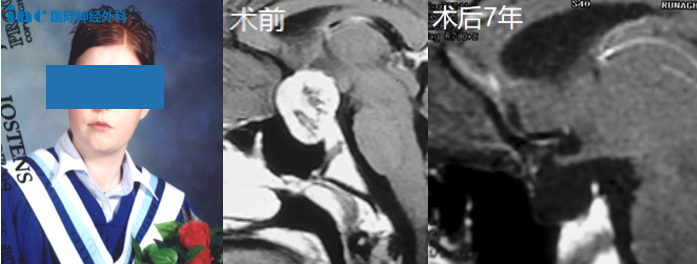

颅咽管瘤的阴霾,笼罩在安达的童年中长达5年,从7岁一直到12岁。不敢轻易手术,怕一手术人就没了,如果只切一点,这种脑瘤也会很快复发,孩子白遭罪了安达的父母彻夜难眠,终究还是无...